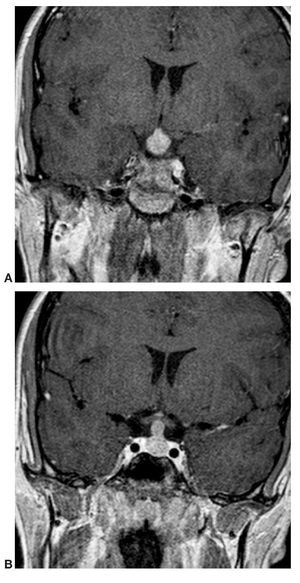

Paciente varón de 14 años de edad, con talla baja y panhipopituitarismo.

Fig. 2.